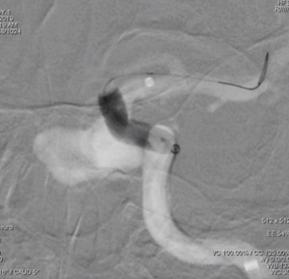

再行造影见动脉瘤不显影,无造影剂渗漏,血管重建满意。

3D重建图示支架贴壁良好。